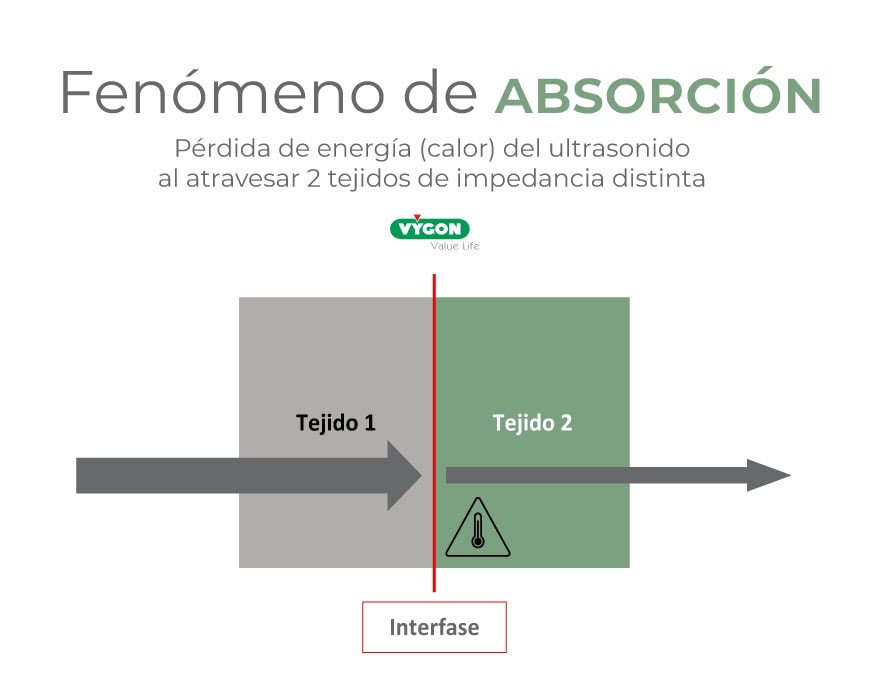

Absorción

Esa energía que pierde el ultrasonido al atravesar el tejido se convierte en calor, imperceptible para el paciente (excepto en la retina, donde existe un riesgo teórico de lesión para el tejido, el ultrasonido se considera inocuo para el cuerpo humano).